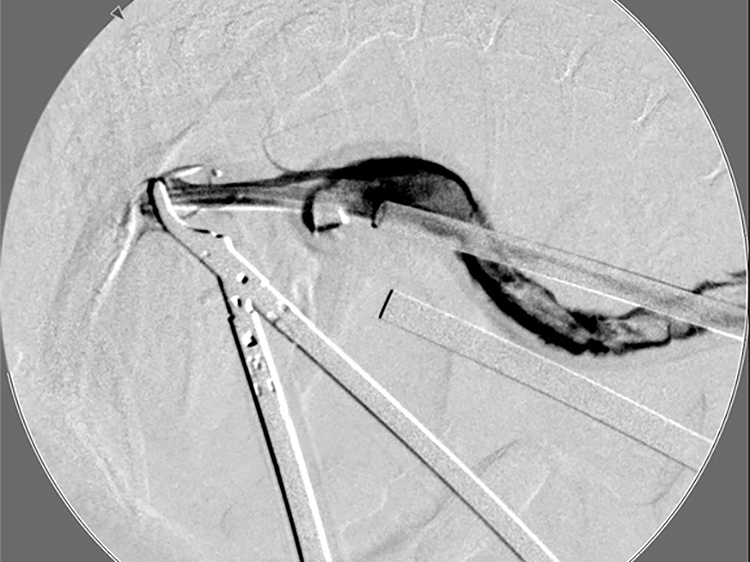

胆嚢の通路がちゃんと開通しているのか調べるために造影検査をしています。 この処置をすることで洗浄の効果と詰まりを確認することができます。

総胆洗浄をして詰まりがないかまずは確認します。

きれいに開通していました。鉗子が大きく感じますが体が小さいので大きく見えます。

詰まりがないかを透視で確認しています。